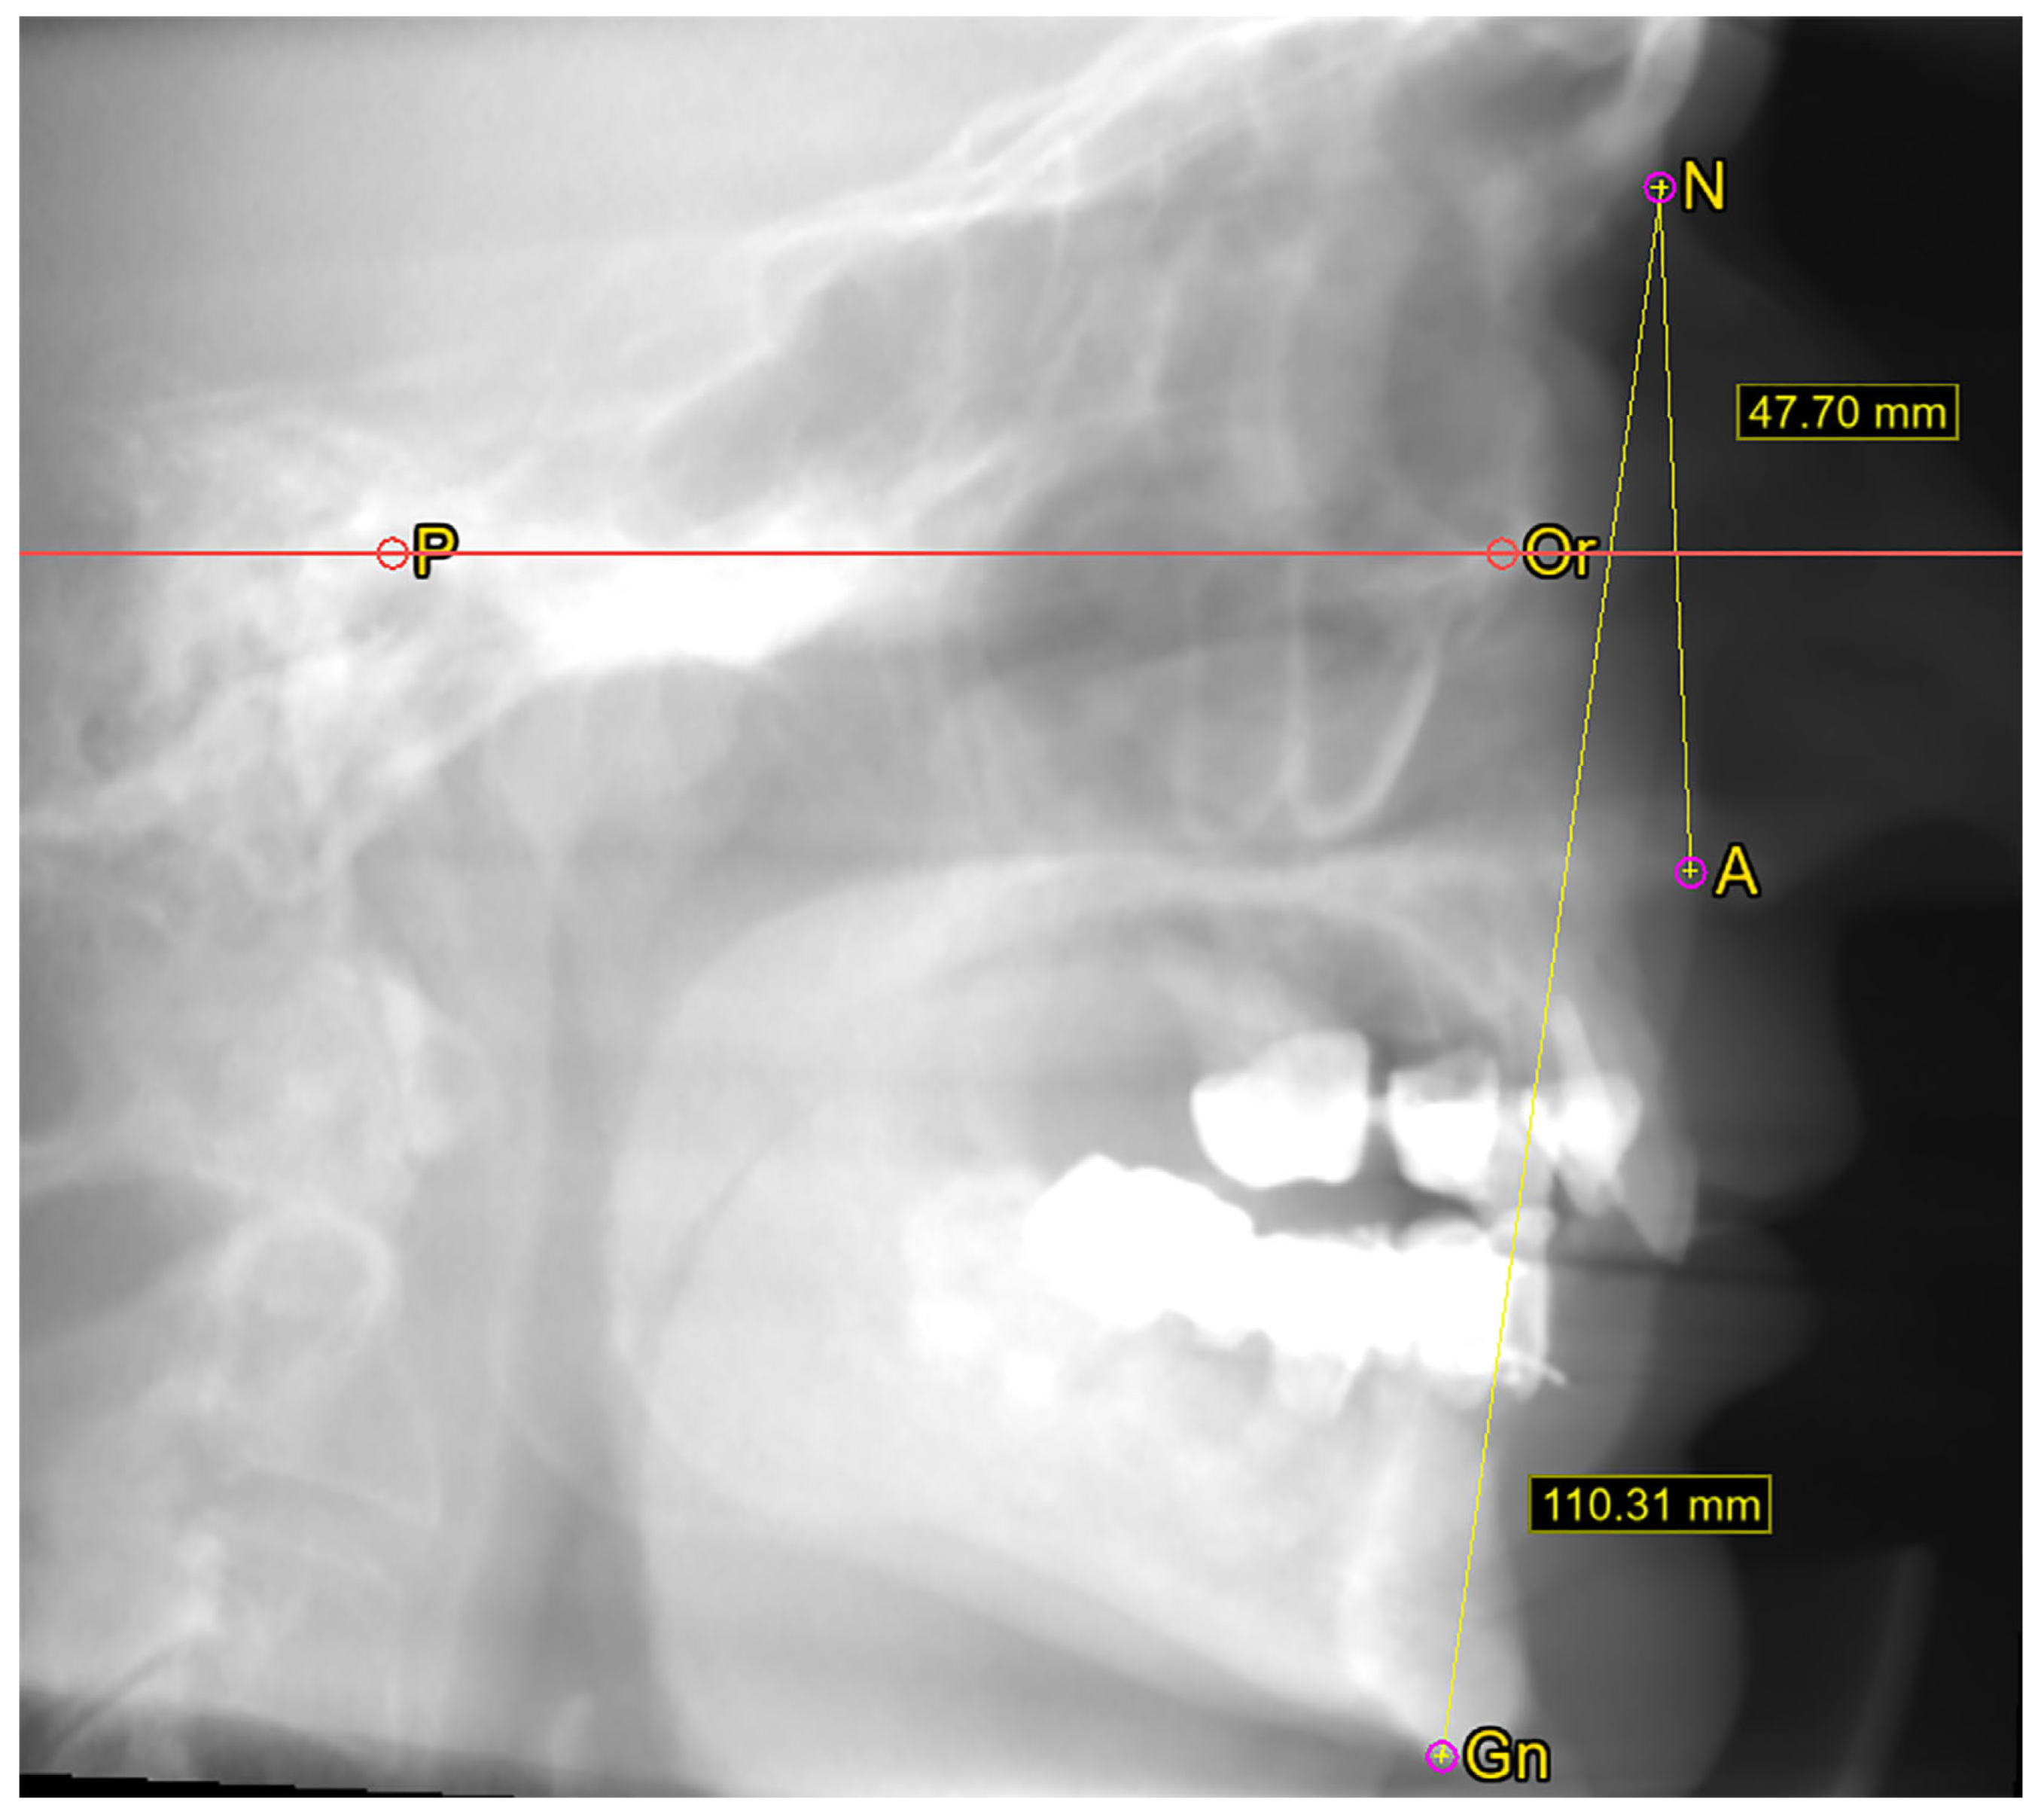

2.2. Cephalometric Measurements

3.2.2. Midface Height

3.2.3. Facial Height

3.2.4. Facial Index